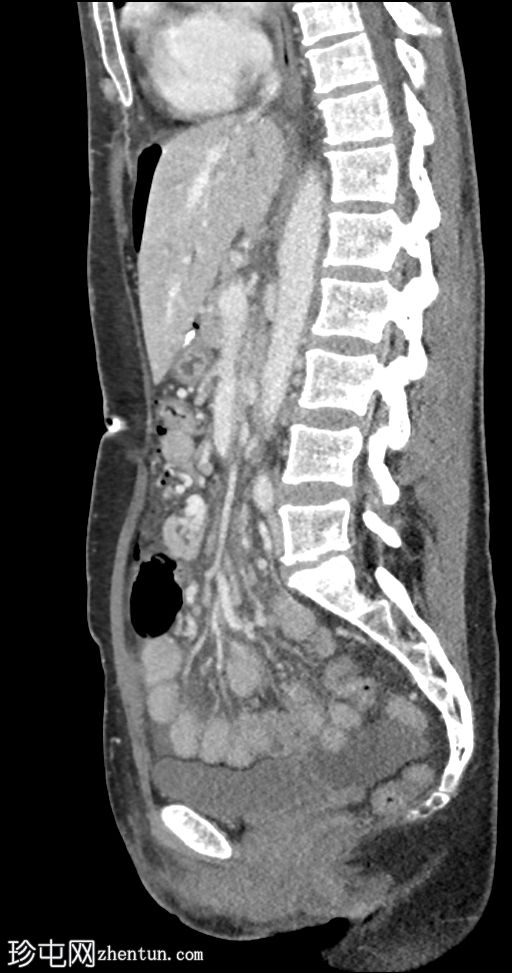

矢状位增强扫描(门静脉期)

大量游离液体和游离气体。游离气体回流至邻近的胃空肠吻合口,伴有肠壁缺损和小肠壁增厚。

漩涡征和肠系膜静脉淤血。左下腹和盆腔内可见肠壁增厚但强化的小肠袢。

患者被送入手术室,术中证实存在内疝(CT上的漩涡征提示),并伴有小肠袢缺血。同时发现并修补了穿孔性边缘性溃疡。减重手术是内疝的危险因素。